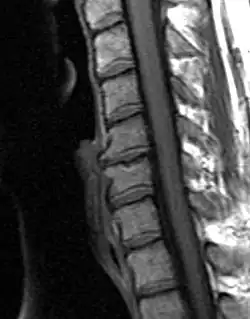

| Degenerated disc between C5 and C6 (vertebra at the top of the picture is C2), with osteophytes anteriorly (to the left) on the lower portion of the C5 and upper portion of the C6 vertebral body. | |